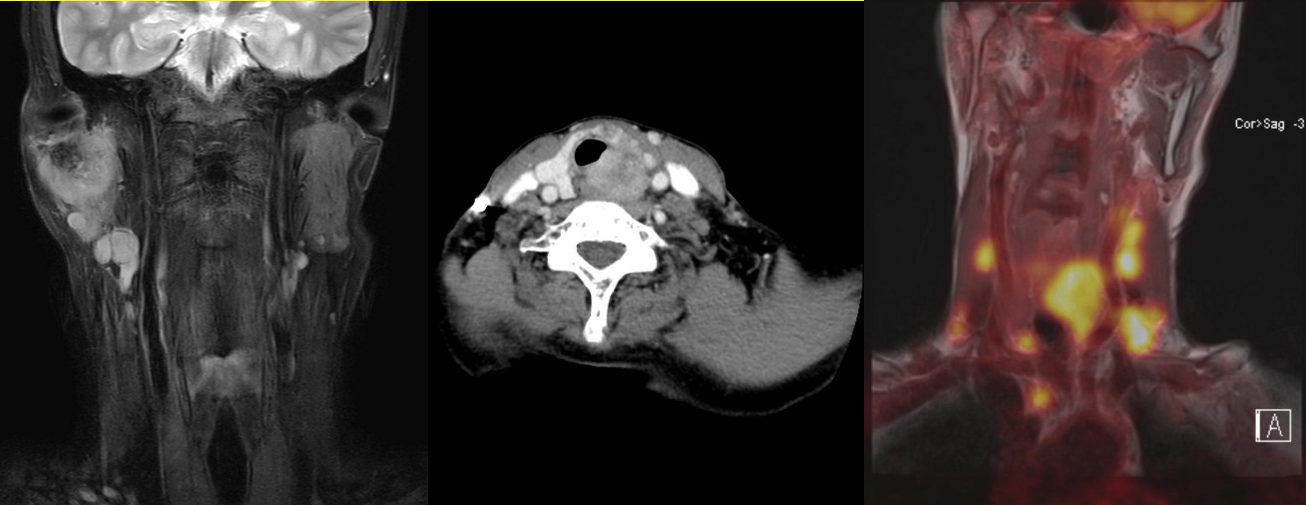

두경부암의 진단의 경우에는 크게 신체검사와 영상검사를 통해서 진단하게 됩니다. 신체검사의 기본은 이비인후과적 내시경 검사이며 이때 환자가 호소하는 증상과 연관된 부위를 중심으로 증상을 유발할 수 있는 모든 부위를 내시경으로 자세히 검사하게 됩니다. 두경부암의 경우 경부임파선 전이가 드물지 않기 때문에 양손을 이용하여 전문의가 시행하는 경부 촉진검사 또한 매우 중요합니다. 원발부위로 의심되는 병변이 발견될 경우에는 접근이 쉬운 부위의 경우 외래에서 조직검사를 바로 시행하며, 후두암이나 하인두암 같이 외래에서 조직검사가 용이하지 않은 부위는 조직검사 및 병변의 진행정도 평가를 위해서 전신마취를 해야 할 수 있습니다. 또한 경부전이 여부를 정밀검사 하기 위하여 경부 전산화단층 촬영(CT) 및 초음파 검사를 시행하게 됩니다. 마지막으로 진행된 두경부암의 경우에는 최종 치료 방침을 결정하고 치료를 시작하기 전에 원격전이가 없는지 여부 확인을 위해서 PET 검사를 추가로 시행하게 됩니다.

진행된 갑상선암의 경우 암이 갑상선뿐만 아니라 주변의 근육, 신경, 기관지 및 식도를 침범한 경우가 많고 대부분의 환자에서 경부임파선 전이가 동반되기 때문에 수술을 해야 합니다. 또한 진행된 갑상선암의 경우 침범된 기관지 및 식도를 악성종양과 함께 제거하며 동시에 결손 부위에 대한 재건이 병행되어야 합니다. 본 센터에서는 세계적 수준의 경험과 결과를 보고하고 있습니다.

침샘암 (이하선암), 기도와 식도를 침범한, 다수의 경부임파선 전이를 동반한 진행된 갑상선암